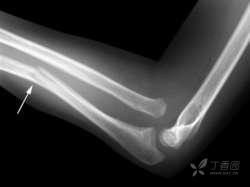

桡骨小头骨折